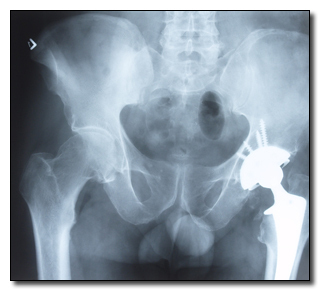

Everything from your car to your blender is getting upgraded with a computer chip these days. Medical implants like pacemakers are no exception. Since they need to be updated somewhat remotely anyway (otherwise all maintenance would involve major surgery), they do have limited outside connectivity, allowing doctors to access your stored medical history, your name and address and your doctor's name and address. Oh, and a skilled hacker can access all of it, too.

That's right: They can hack your goddamn heart.

And as if we need to say it: Obviously they can remotely stop it beating while they're in there.

Photos.com

In some devices, like an implanted defibrillator, which shocks your heart back into activity if it ever seizes up, hackers can remotely shut off the device and wait for you to die or, if they just ain't got all day, send it into test mode instead -- where the pacemaker repeatedly delivers powerful, fatal shocks to the heart even when it's already beating just fine.

Via Wikimedia Commons

Diabetic implants like insulin pumps have proven to be another security risk: When hackers get access to one of these devices, they can mess with the levels being injected into the body, which, again, can have fatal consequences. Jay Radcliffe discovered this hack while he was dicking around with his own diabetic equipment. At first he thought it was "really cool" that he could just ditz around for a few minutes and gain access to computers within his own body. Then he realized that any bored teenager with the right skill set could have total mastery over whether he lives or dies.